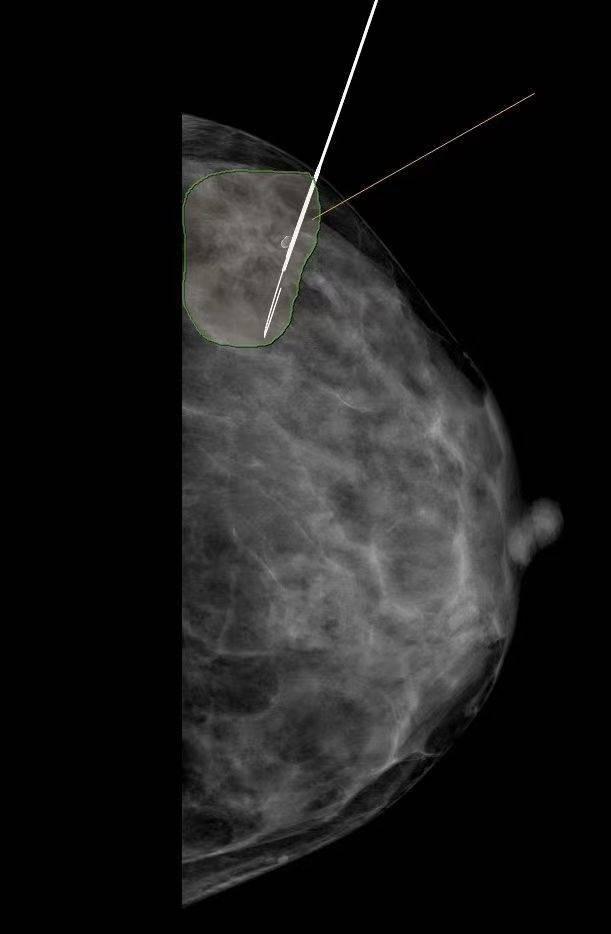

患者为46岁女性,因体检时发现左乳结构扭曲,有恶性肿瘤的可能,患者极为焦虑,来院要求切除病灶。经肿瘤甲乳外科、影像中心、超声医学科多学科专家联合会诊(MDT)讨论后,决定为患者实施在X线引导下进行病灶定位,以完整切除病灶。

因为乳腺组织是一个球体结构,穿刺定位比较困难,不仅需要精准的定位病灶位置,还需要熟练的拍摄技巧给予配合,对影像中心医务人员的技术能力是一次严格的考验。

在技术员张云及黄纯莉等医师的通力配合下,定位针准确穿入病灶内,并调整好位置,为手术的顺利进行做好前期保障工作。

对于临床不可触及、超声阴性仅钼靶X线显示结构扭曲及钙化的病变,在乳腺X线引导下术前定位,可使病变部位得以准确标记,有助于评估病灶范围,指导外科精准切除病灶,最大限度的保留正常腺体,避免良性病变过度手术或恶性病变漏切给患者带来的身体损伤和心理负担。提高了乳癌早期诊治疗效,减低乳腺癌死亡率,更提高了乳腺手术的安全性及保乳手术的开展率。